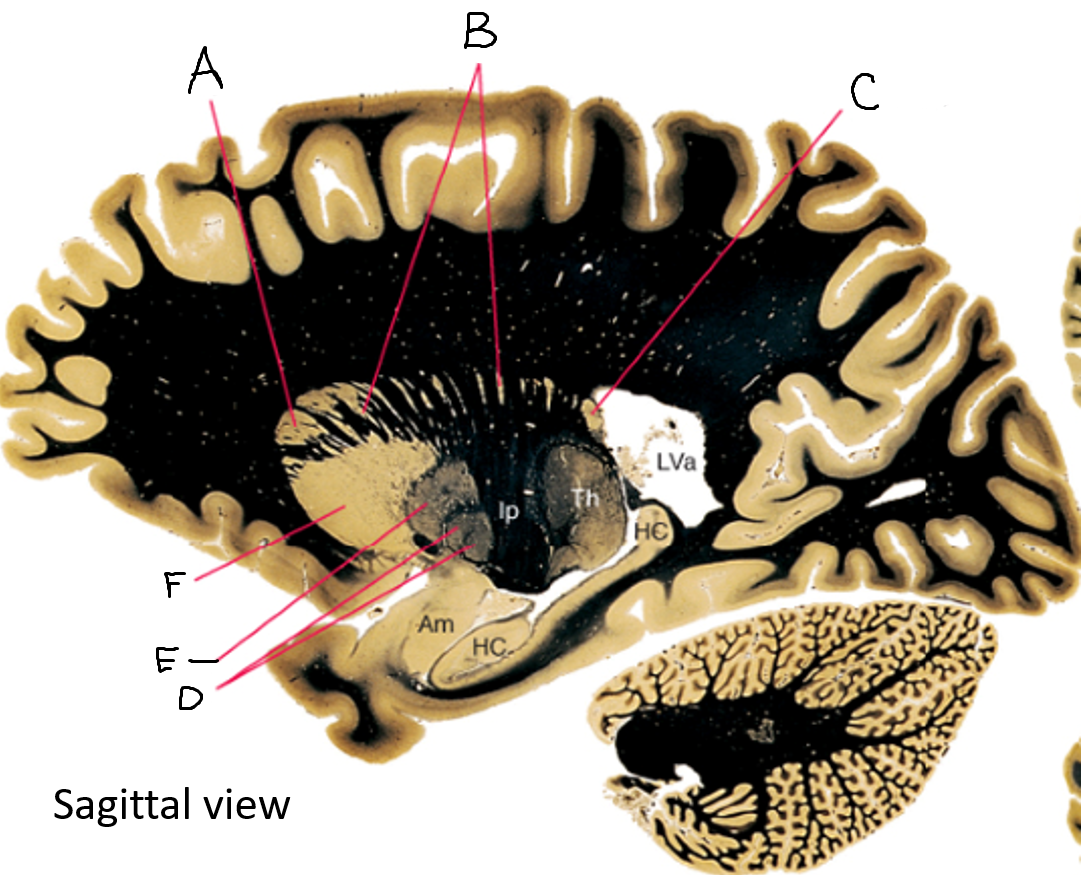

caudate nucleus head

A

Putamen

B

caudate nucleus tail

C

Lateral ventricle

D

caudate nucleus body

E

internal capsule

F